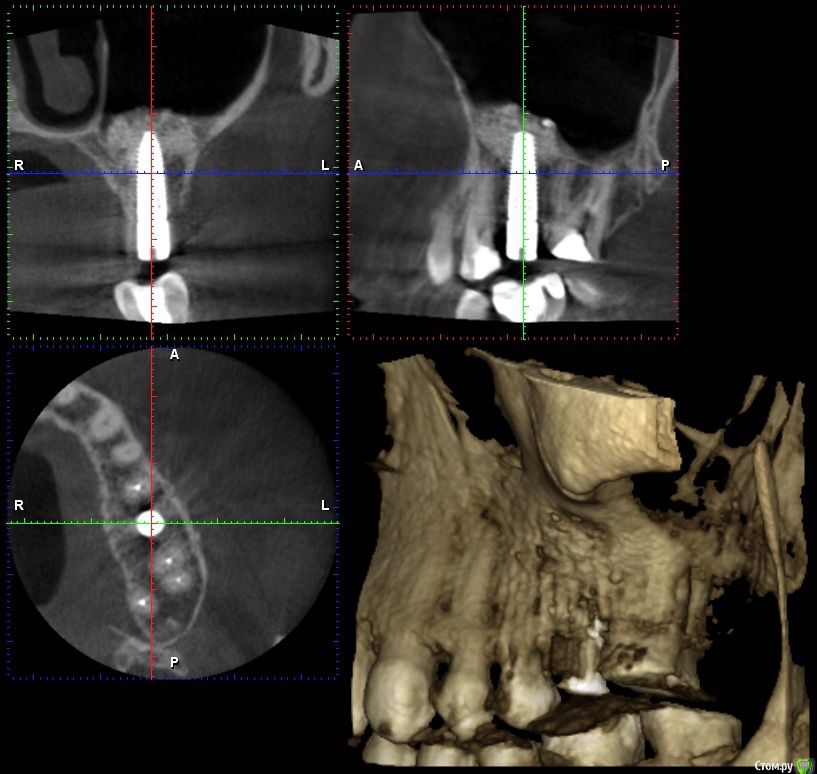

wladdX Опубликовано 26 января, 2017 Поделиться Опубликовано 26 января, 2017 Несколько скринов 2-й сегмент. Ссылка на комментарий

wladdX Опубликовано 26 января, 2017 Поделиться Опубликовано 26 января, 2017 (изменено) 3-й сегмент. Изменено 26 января, 2017 пользователем wladdX Ссылка на комментарий